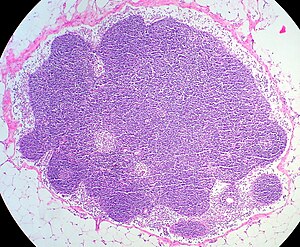

Гистологическая архитектура и клеточные популяции

Зональная дифференцировка паренхимы

Внутренняя архитектура лимфатического узла характеризуется чёткой зональной организацией, отражающей функциональную специализацию различных отделов[6]. Периферические отделы представлены корковым веществом, которое подразделяется на поверхностную кортикальную зону и глубокую паракортикальную область[7].

В верхней части коры находятся группы малых клеток, называемые лимфоидными фолликулами. В этих группах находятся и размножаются B-лимфоцитами. Когда фолликулы активизируются, в их центре образуются зоны, где клетки быстро делятся и становятся более зрелыми. Эти зоны называются герминативными центрами. Вокруг этих центров находится область с большим количеством малых лимфоцитов[7].